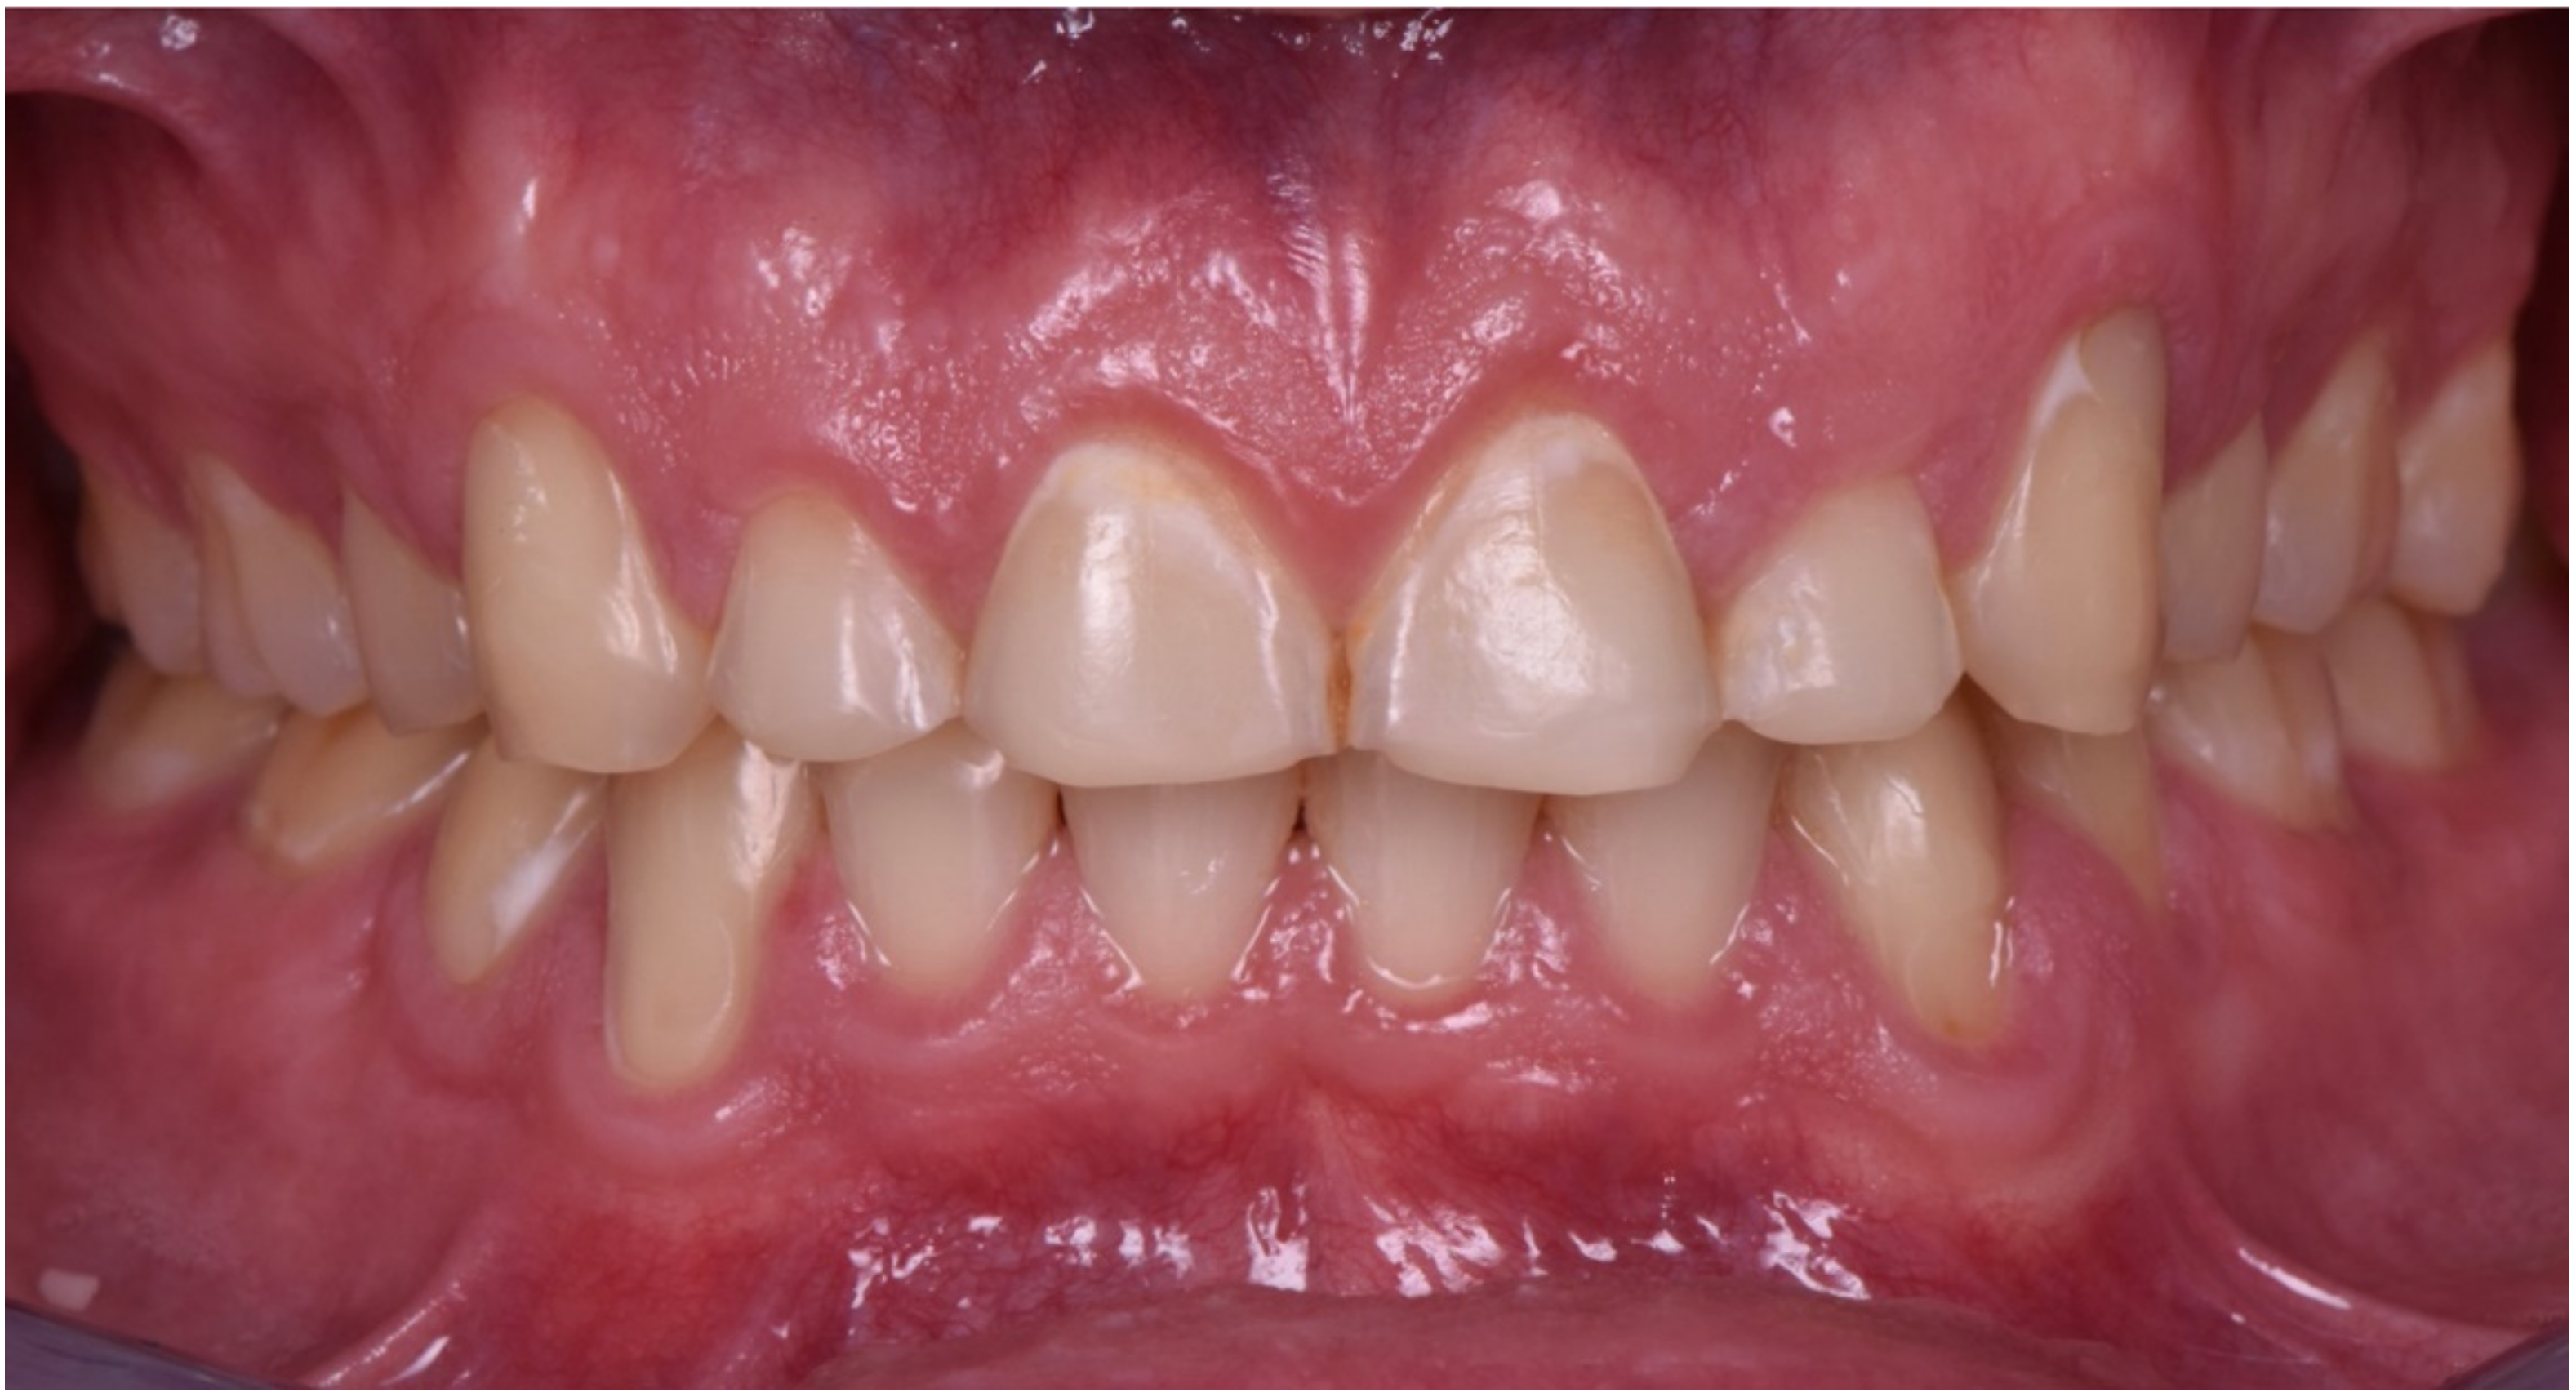

2. Clinical Report

2.1. Planning Phase

2.2. Restorative Phase